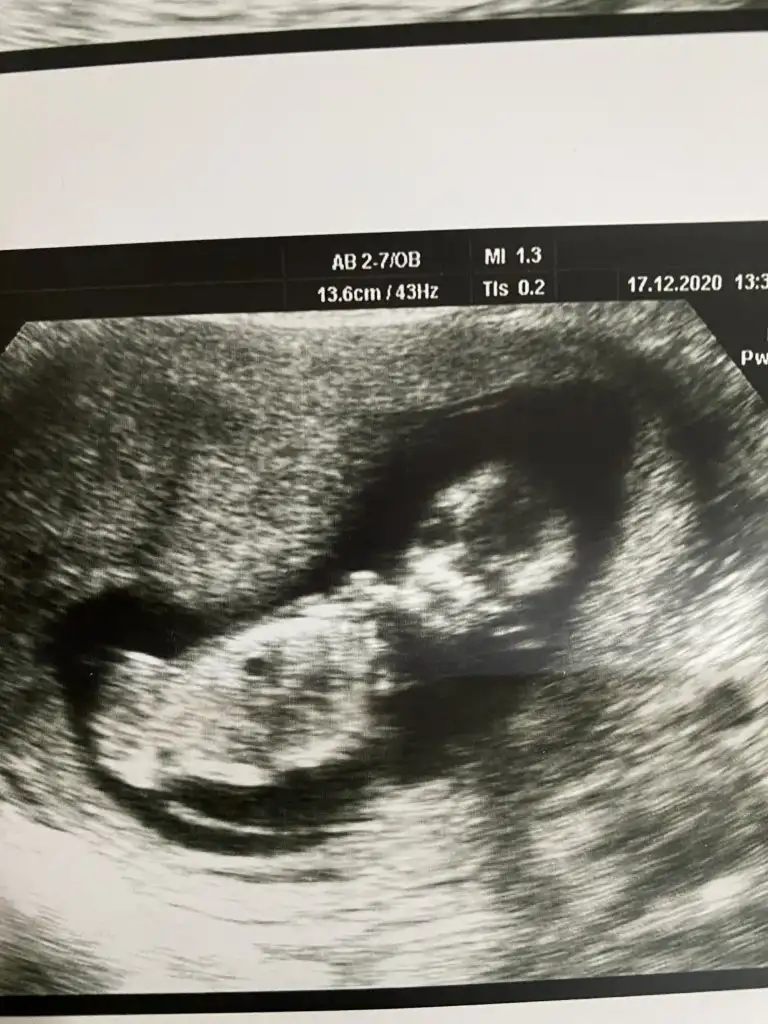

Erkek bebek buBanada bakar misiniz lütfen

Tsk. Ederim. Nasil farkettiniz?Erkek bebek bu